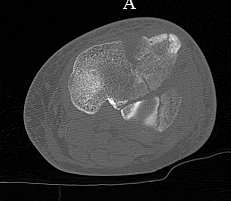

[Ortho] перелом проксимальной тибии + вывих бедра

Серия КТ сканов в аппарате